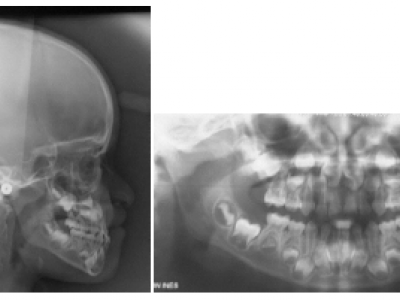

La téléradiographie montre la classe III squelettique et sur la radiographie panoramique on note un manque de place pour les dents définitives aux 2 arcades (Fig.3-9). 15 et 25 peu visibles à ce stade, ont un retard de minéralisation.

Dans le 1er cas, en observant les téléradiographies de profil, on note que bien que les incisives centrales supérieures soient en proalvéolie à la fin de la première phase de traitement (Fig. 8), comme l’occlusion normalisée est obtenue précocement (au moment de l’éruption des incisives), la croissance améliore spontanément leur inclinaison par le redressement des racines (Fig. 9).